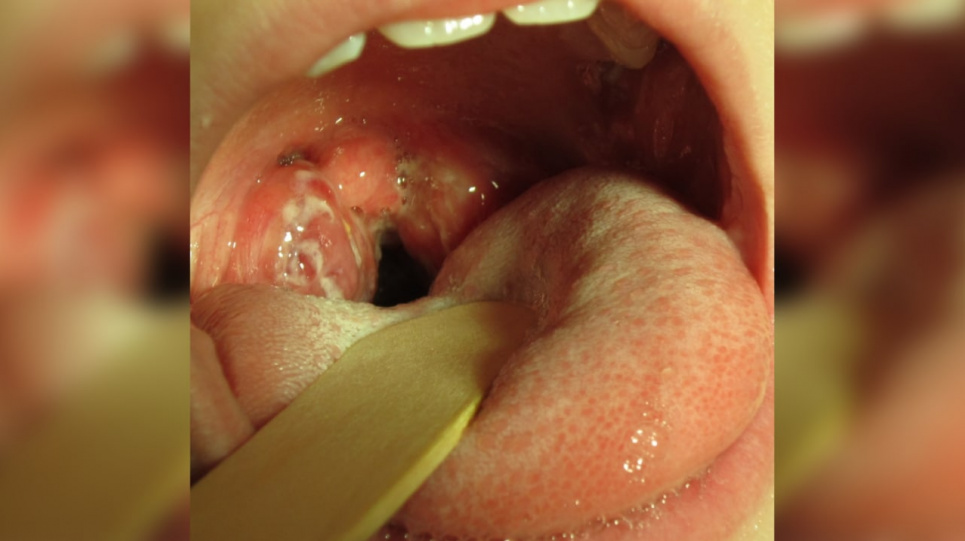

Стрептокок — це бактерія, яка викликає ангіну, скарлатину, зі стрептококом пов’язано багато хвороб, таких як ревматизм, гломерулонефрит, системний червоний вовчак тощо.

Комаровський наголошує, що наразі ми маємо дві унікальні ситуації. По-перше, підйом захворюваності у міжсезоння. По-друге, дуже висока летальність, коли локальним процесом — ангіною — не закінчується: інфекція генералізується, тобто поширюється по всьому організму, «відбувається, говорячи зрозумілою мовою, зараження крові стрептококом, і від цього реально гинуть діти».

Окрім того, при стрептококовій ангіні біль у горлі — головний симптом, він хвилює більше, ніж решта.